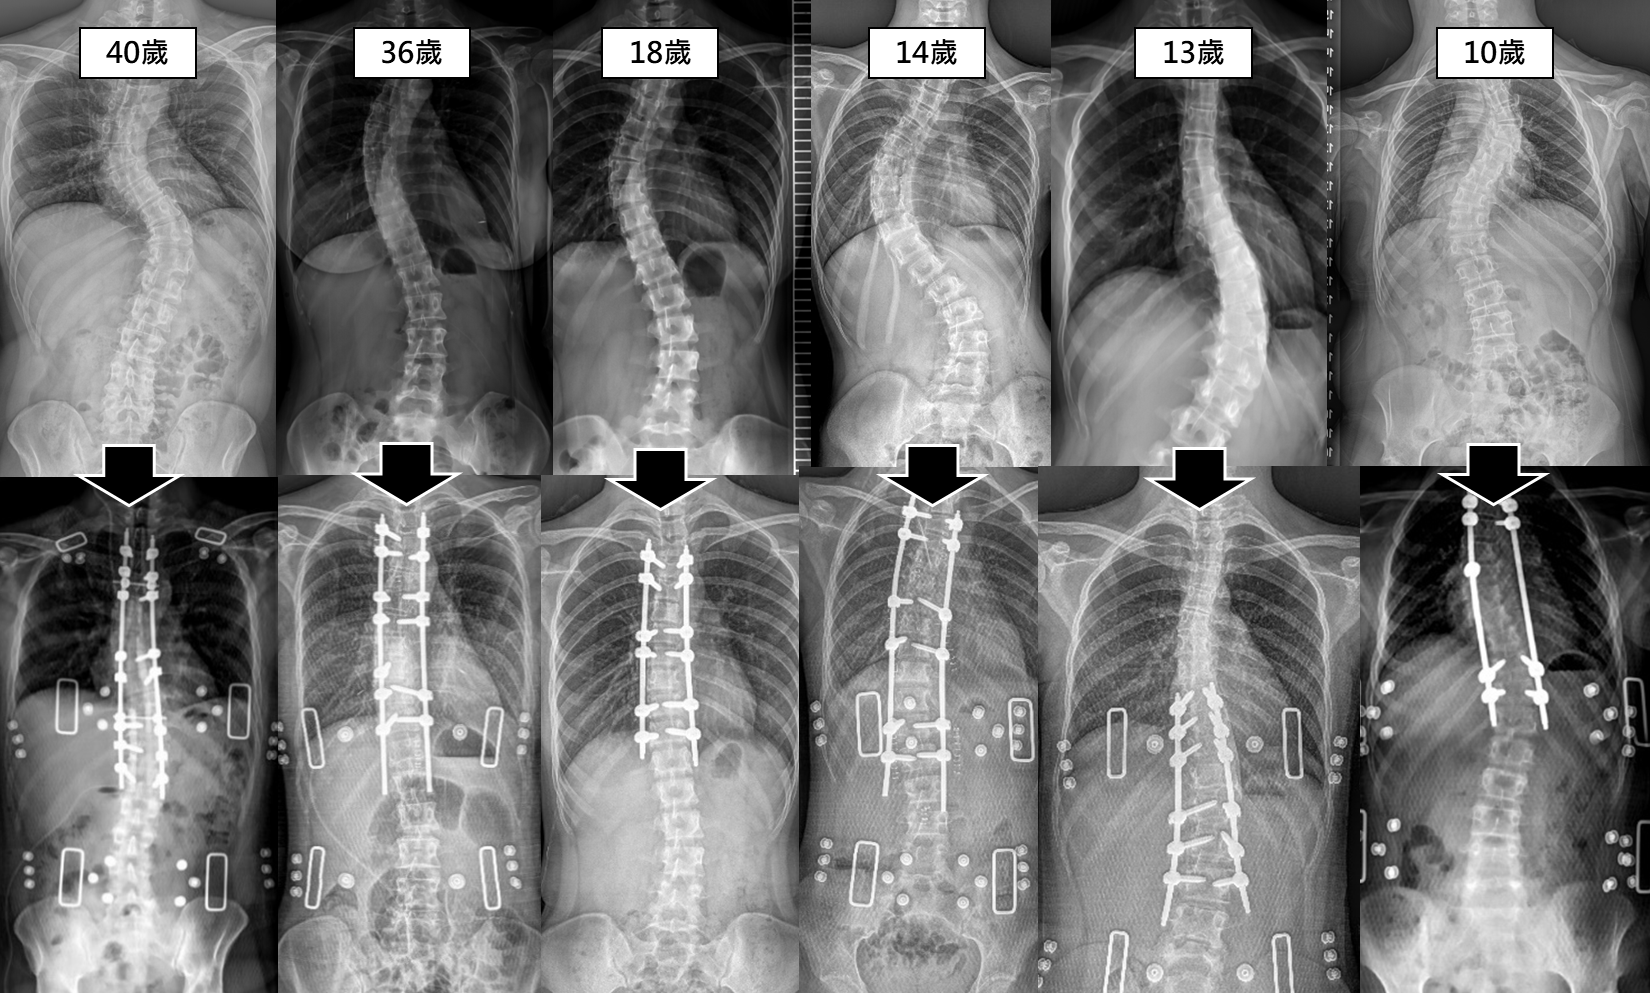

3. 發育中兒童專屬:成長型脊椎側彎矯正手術

對於10歲以下、骨骼尚未發育成熟的早發性脊椎側彎兒童,目標是「在控制側彎的同時,不阻礙脊椎生長」。

-

延長式連接鋼桿:術後需定期追蹤,待患者渡過成長期後,可以透過手術永久固定。

| 成長型支架 |

10 歲以下 發育中兒童 |

兼顧矯正與脊椎生長發育 |

需長期追蹤 定期調整長度 |